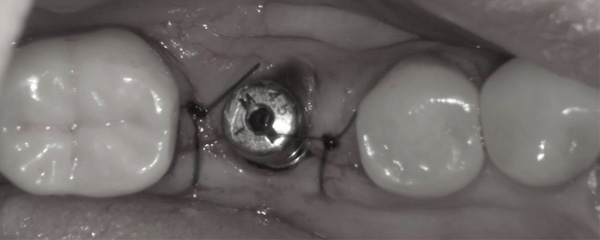

初診時口腔内写真。

他院さんで15年前に入れたインプラントの上部構造(セラミック歯)が壊れて、来院されました。

ここ最近5年間は歯科医院に通っていなかったようで、インプラント周囲炎(インプラントの歯周病)にもなっており、膿が絶えず出ている状態でした。

古いインプラント周囲の歯茎を切って開きます。

専用ドリルで、古いインプラントを撤去します。

古いインプラントの直径が4ミリなので、内径が4ミリ外径が5ミリの撤去用ドリルを使用しました。

わずか5分で古いインプラントの撤去が完了しました。

代わりとして直径5ミリ長さ8.5ミリのサイズのインプラントを埋め込んでいきます。

新しいインプラントが、同じ位置に収まりました。

専用ドリルを活用することで、患者様の負担を最小限にすることができます。

2本だけ縫ってオペ終了となります。

トータルのオペ時間が僅か15分のみ。

シンプルな処置に徹することで、術後の痛みと腫れもありません。